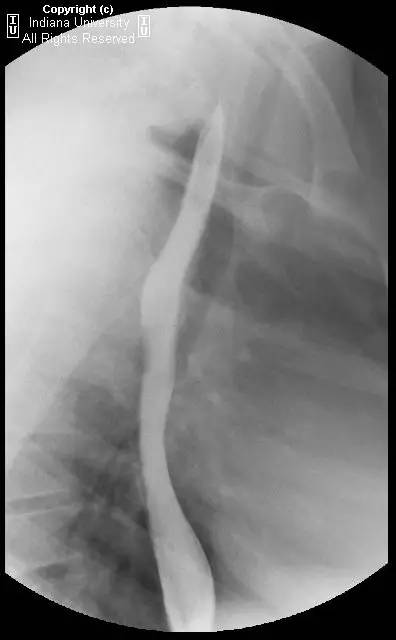

【影像学表现】可见小滑动性食管裂孔疝,食管远端胃食管连接处上方亦见一小的边界清晰的环形充盈缺损,钡剂通过顺利,但直径13mm不透射线的药片吞水后仍在充盈缺损上方崁顿,数分钟后进入胃。

【诊断】Schatzki环(舍茨基环)并滑动性食管裂孔疝

Schatzki ring andsliding hiatal hernia.